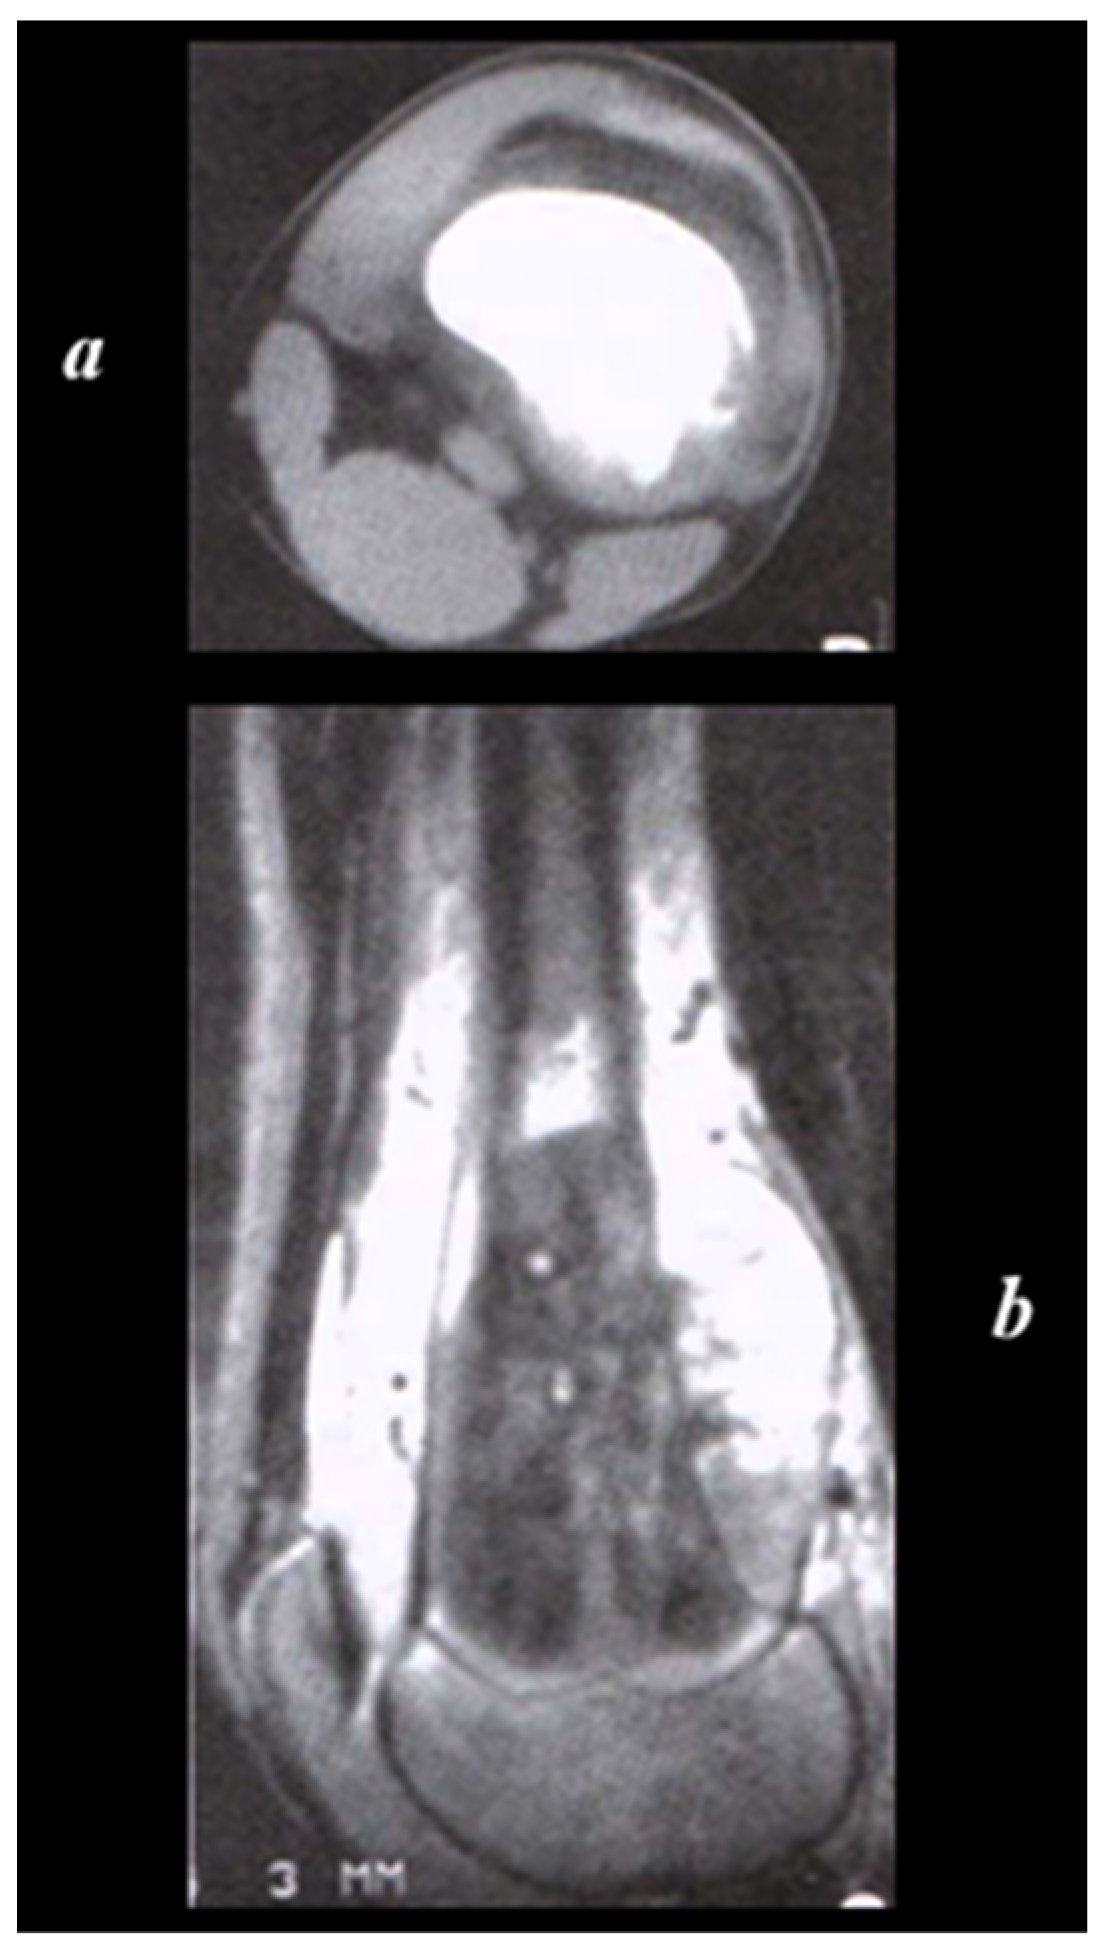

Sarcomatous osteogenesis induces the appearance of linear, coarse, thick “sunray” calcific beams implanted perpendicular to the axis of the bone (Figure 3).

Figure 3. A 9-year-old child’s left knee joint and leg were radiographed in AP and lateral projections. A sclerotic lesion involving the diametaphyseal region of the tibia with a broad zone of transition, osteoid matrix, periosteal elevation (Codman’s Triangle), and the distinctive “Sunburst” type of periosteal reaction is seen on radiographs. There is no discernible intra-articular extension or soft tissue involvement. Radiopaedia.org.